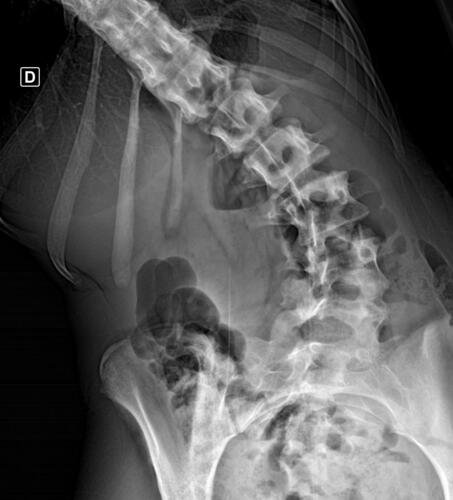

A Vá tem 13 anos e precisa urgentemente realizar uma cirurgia na coluna.Valentina foi surpreendida com o diagnóstico de escoliose hepática grave com 67 graus de desvio (desvio longitudinal da coluna), e precisa realizar com urgência a cirurgia corretiva, os exames foram realizados em Porto Alegre, mas a cirurgia está marcada para dia 13/07 em São Paulo devido a gravidade do caso, para isso a família terá que ficar residindo próximo ao hospital em São Paulo por no mínimo 30 dias para uma plena recuperação. Sabemos bem que qualquer procedimento cirúrgico é delicado, na coluna então nem se fala.Após o diagnóstico e o prognostico dessa doença a família se desfez de alguns bens (carro e moto) para cumprir os prazos dos exames e consultas, necessitando agora arrecadar o valor para a estadia da pequena Valentina e seu pós operatório (medicação, consultas e fisioterapia).

Em anexo os exames (laudo e imagens) para expressas a gravidade do caso.